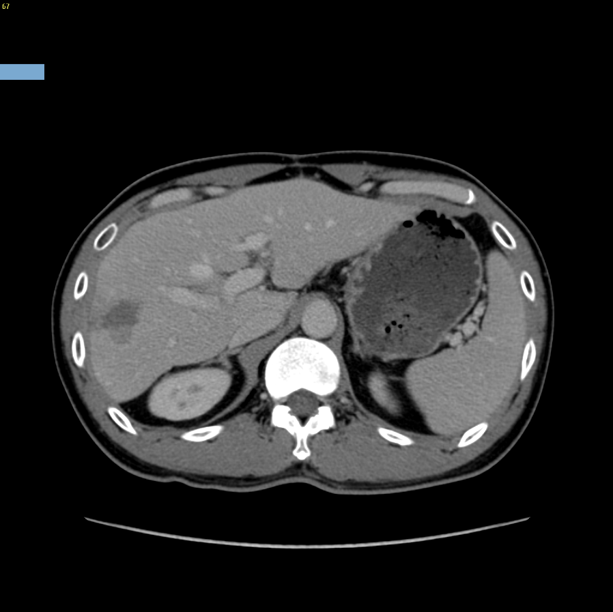

右肝癌复发-门静脉栓塞+肿瘤动脉栓塞后右半肝切除